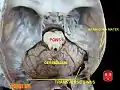

Dura mater and its processes exposed by removing part of the right half of the skull, and the brain The sinuses at the base of the skull

Left temporal bone showing surface markings for the tympanic antrum (red), transverse sinus (blue), and facial nerve (yellow) Transverse sinuses

Transverse sinuses Transverse sinuses

Transverse sinuses